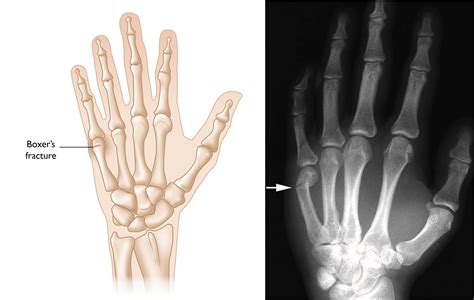

Not all injuries require surgery, but professional imaging is non-negotiable. An X-ray is the only way to confirm a broken pinky finger. A doctor will determine if the bone is fractured in a way that requires a splint, "buddy taping," or in severe cases, surgical pinning to realign the bones.

• broken pinky finger xray